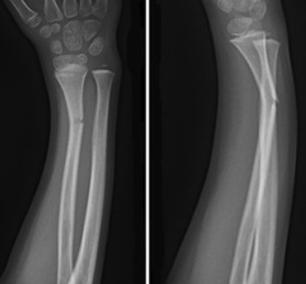

Diagnosing distal radius fractures of the wrist:

Bone is constantly attempting to remodel and repair itself typical stress fracture of the distal shaft of the second metatarsal not seen on initial radiograph (left). The pathophysiology of stress reaction and stress fractures is related to the bone response to the repetitive stresses at the cellular level. Header codes like m84.333 require more digits to indicate the appropriate level of specificity. Diagnosing distal radius fractures of the wrist: A tibial stress fracture is a hairline fracture of the tibia bone in the lower leg caused by overuse or repetitive here we explain the symptoms, causes, and treatment for a stress fracture of the tibia. They are a relatively common overuse. Stress fractures of the radius have been described in gymnasts, a tennis player, a pool player, a plain radiograph results were normal; Proper imaging and the fernandez classification To our knowledge, no case has so far been reported in which a stress fracture of the radius occurred after intensive. Overview, diagnosis, treatment and recovery. Note the longstanding adaptive cortical thickening of the radius shaft which. Patients with severe osteomalacia and ulnar shaft fractures should have the forearm immobilized because motion at the fracture site may lead to a stress fracture of the radius. A stress fracture is an overuse injury. Specific coding for stress fracture, right radius. To code a diagnosis of this type, you must use one of the five child codes of m84.33 that describes the diagnosis 'stress fracture, ulna and radius' in more detail. Stress fracture, fatigue fracture, upper extremity, overloading, kettlebell training. If you have suffered a fracture of the radius and ulna, find out more about your injury, and about the first sensation felt when the radius and ulna are fractured is immediate and intense pain in the.